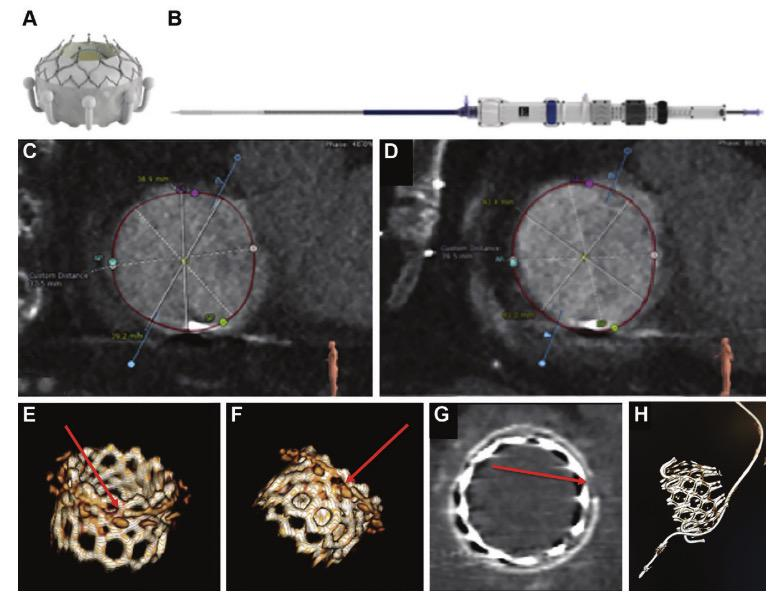

在经导管三尖瓣植入术的术前和术后评估上,CT也发挥了非常重要的作用。

下图为经导管三尖瓣植入术(EVOQUE,Edwards Lifesciences)的术前和术后CT扫描图像(Ref 44):

A:Evoque心脏瓣膜,包含一个自膨胀的镍钛合金框架,带有牛心包叶、环内密封裙和心室锚。

B:28-F Evoque三尖瓣系统

C:收缩期的横断面测量

D:舒张期的横断面测量

E-G: 一名因生物瓣膜植入术失败的患者接受瓣膜内SAPIEN 3瓣膜置换术,在术中需要折断生物瓣膜。

E-F:VR图显示生物瓣膜折断:生物瓣环在球囊扩张过程中被折断(箭头),以允许足够的导管瓣膜植入扩张。

G:多平面重建图显示生物瓣膜折断。

H:48-mm的EVOQUE瓣膜植入后的VR图像:术后心脏CT证实起搏器导线位于植入物外部,排除起搏器导线断裂风险。